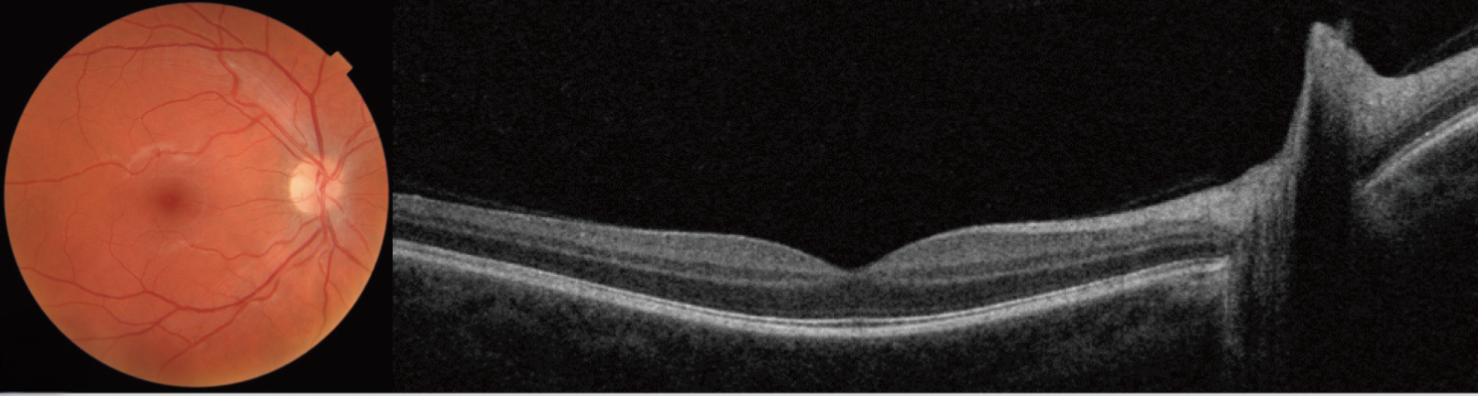

Optical Coherence Tomography (OCT)

What is Optical Coherence Tomography (OCT)?

OCT is a state-of-the-art, non-invasive imaging technology that provides high-resolution, cross-sectional images of the retina, cornea, and optic nerve.

This painless scan allows your Optometrist to see the individual layers of the eye in remarkable detail - offering a level of insight that isn’t possible with standard eye exams.

OCT is especially valuable for detecting early signs of eye conditions such as:

Glaucoma

Age-related macular degeneration (AMD)

Diabetic retinopathy

Retinal swelling or thinning

By identifying even the subtlest changes, OCT plays a critical role in diagnosing, monitoring, and guiding treatment decisions - helping protect your vision for the long term.